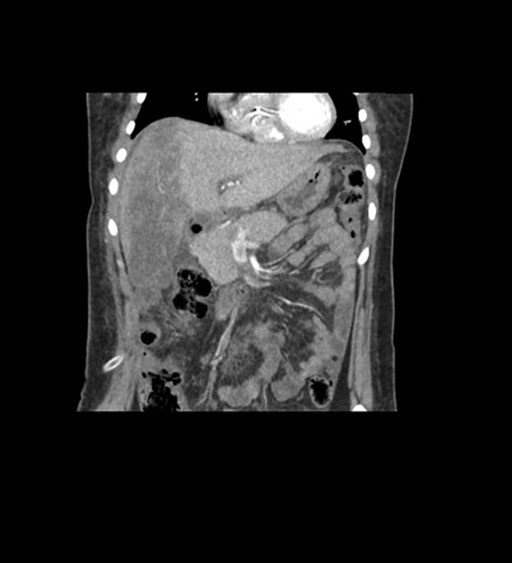

Coronal Venous